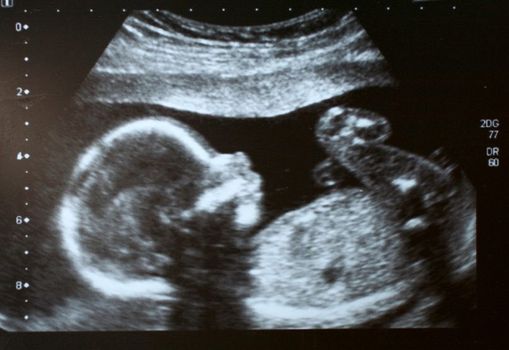

After a few days in hospital Aoife was discharged and told to return in three days for a scan – which she anxiously did.

“My consultant met me at the scan, and pointed out the baby’s heartbeat (relief!) and then asked had I had any gushes since being in the hospital. I said yes, but I’d been bleeding so much that I didn’t think anything of it.”

The consultant told Aoife that the membrane around the baby had ruptured and there was no fluid supporting the baby.

Aoife had two scans prior to travelling. The second scan was just before she was due to leave.